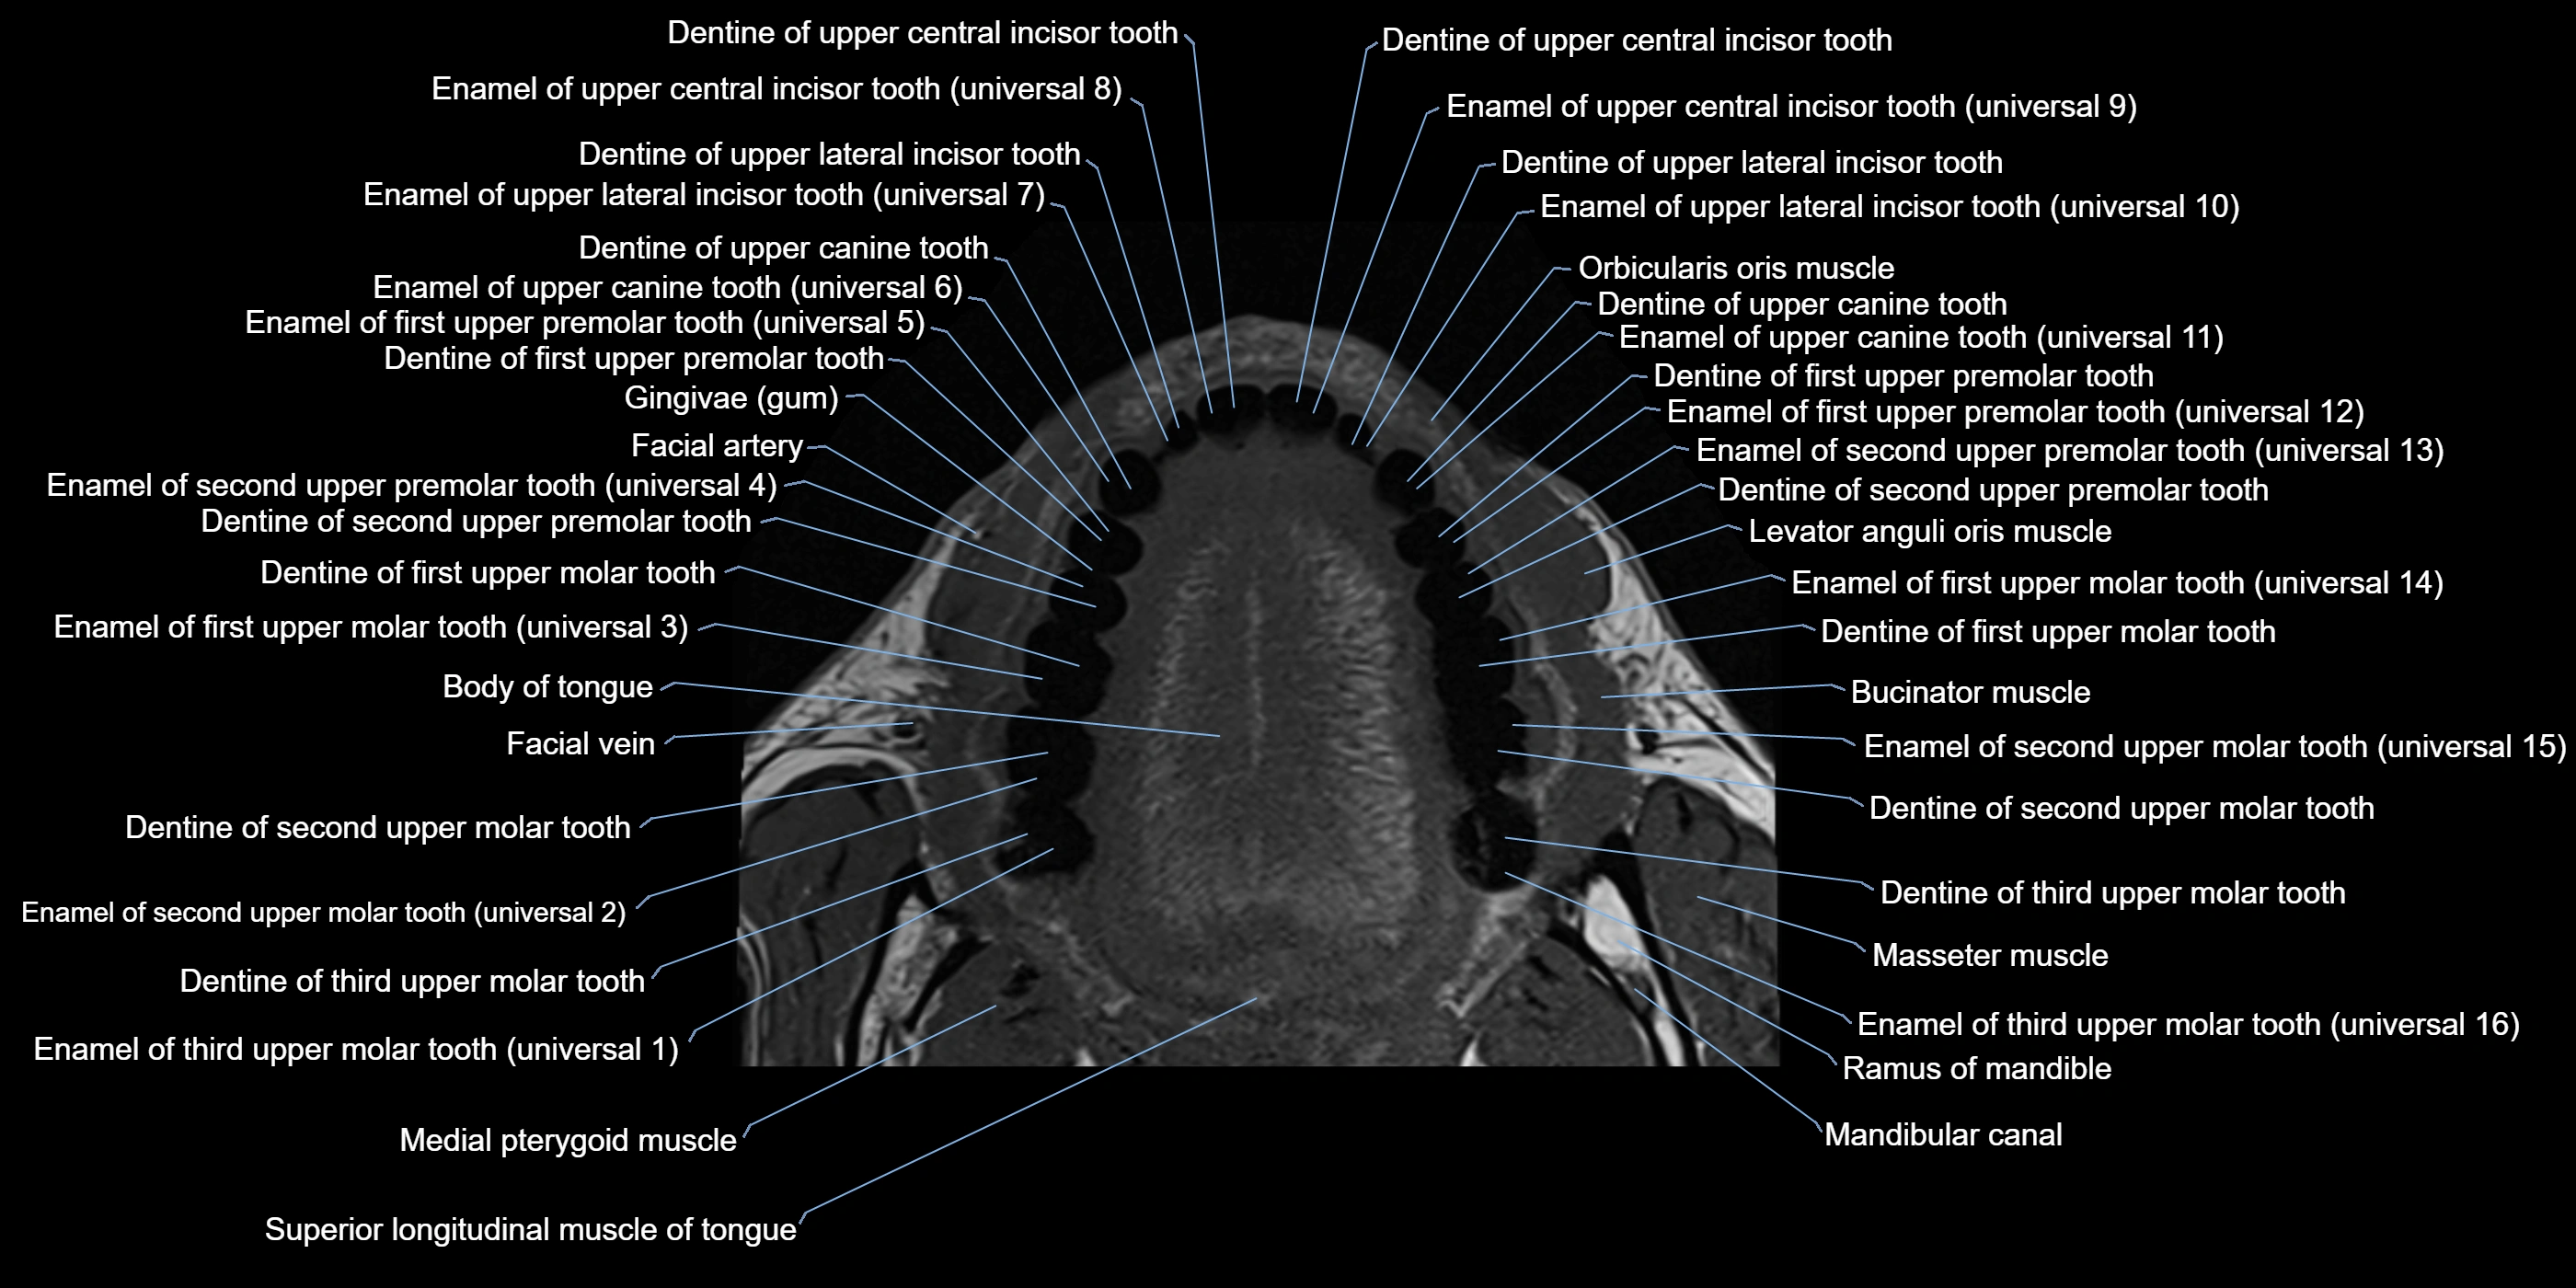

- Buccinator muscle

- Levator anguli oris muscle

- Masseter muscle (Deep part)

- Masseter muscle (Superficial part)

- Orbicularis oris muscle

- Ramus of mandible

- Superior longitudinal lingual muscle

- Superior longitudinal muscle of tongue